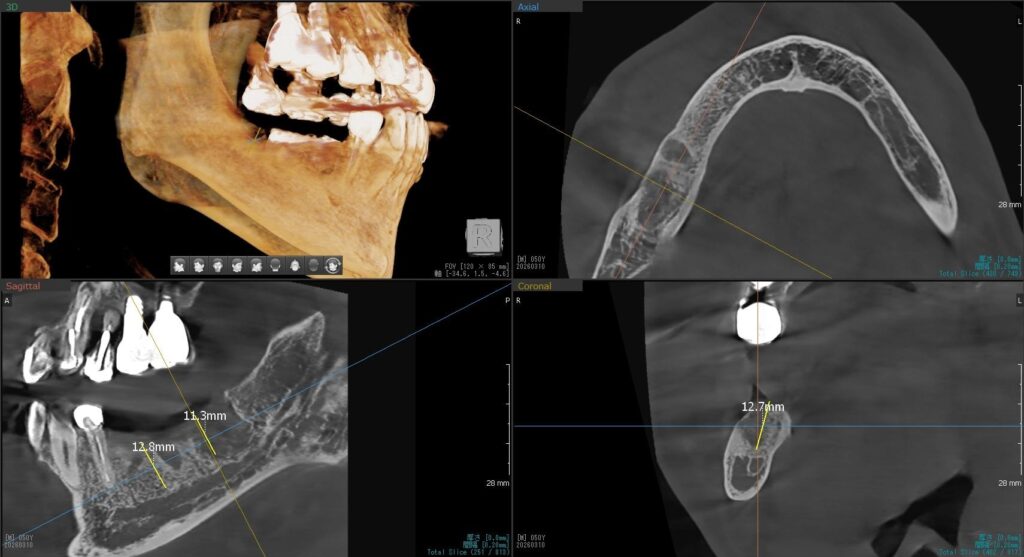

今回の患者様はインプラント植立を希望され、右下5番目・6番目・7番目の合計3本植立が決まりました。

ドリルの先端を細い物から徐々に大きい物に変えながら、植立するインプラント体のネジの部分を除いた胴の部分の太さに合わせた大きさの穴を開けていきます。

開けた穴に、専用道具を使ってネジを締めるように長さ2センチ程のインプラントを骨に埋め込んでいきます。